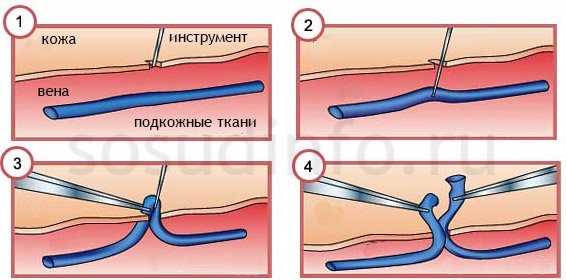

Часто флебэктомия включает полное удаление пораженных вен. В большинстве случаев для этой процедуры не требуется общий наркоз — хирург использует местную анестезию. Пациент остается в сознании, но не испытывает боли. Важной мерой безопасности является фиксация тела пациента на операционном столе, что предотвращает непроизвольные движения, которые могут быть опасны.

Не будем углубляться в детали всех методов флебэктомии. Упомянем, что стандартной практикой является выполнение разреза кожи в дистальных и проксимальных участках конечности, где наблюдается варикозное расширение.

Через эти разрезы удаляется пораженный венозный ствол. Завершающим этапом операции является ушивание мест разрезов. В случаях с тяжелыми формами заболевания может потребоваться комбинированная флебэктомия.

- Кроссэктомия. На этом этапе важно остановить кровоток. Для этого производится перевязка и пересечение поверхностных вен, что осуществляется в области бедренной паховой складки или иногда в подколенной зоне.

- Стриппинг. С помощью дуплексного сканирования определяются пораженные участки вен, после чего удаляются стволы. Обычно затрагиваются большие продольные вены, в то время как голени остаются менее подверженными патологии. Наиболее распространенной процедурой является короткий стриппинг, при котором вена удаляется через прокол в области голени и разрез в паху. Существует несколько операционных техник, включая Зонд Бебокка, криоскриппинг, инверсионный и PIN-стриппинг.

- Пресечение коммуникативных вен. Если коммуникативные вены расположены близко к поверхности кожи, применяется малотравматичная методика. В случае глубокого залегания сосудов врачи используют эндоскопическое оборудование. Этот подход позволяет избежать заметных шрамов и ускоряет процесс восстановления после операции.

- Микрофлебэктомия. Этот вид хирургического вмешательства сочетает в себе высокую косметическую эффективность и результативность. Под местной анестезией выполняются небольшие кожные проколы, через которые удаляются поврежденные участки сосудов и варикозные узлы. Удаление вены осуществляется с помощью специального крючка, швы не накладываются, а шрамы практически отсутствуют.